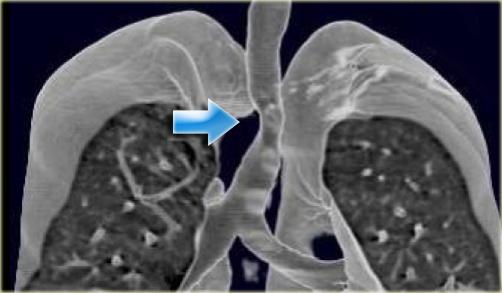

Pulmonary Sling

On the left a 4 month old girl with abnormal echo, benign heart murmur and no respiratory or feeding difficulties.

The sagittal reconstruction shows an anomalous vessel on the posterior side of the trachea.

There is a little mass effect on the trachea.

In pulmonary sling the left PA originates from the right PA and courses between the esophagus and the trachea, where it compresses the right main bronchus.

Pulmonary sling is seen more frequent in children as it is more symptomatic than in adults, because the chest is smaller, but you can also encounter it in adults.

On the left images of a child with wheezing and dyspnea.

The left PA comes off the right PA and runs between the esophagus (with nasogastric tube) and the trachea.

Some of these patients also have long segment stenosis in the trachea because of cartilagenous rings.